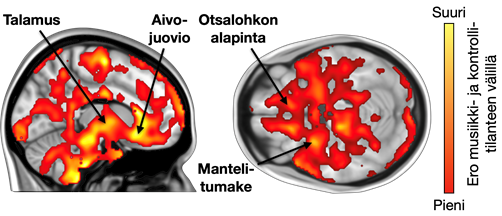

Tulokset osoittavat, että lempimusiikki vaikutti opioidien vapautumiseen useilla aivojen alueilla, jotka on liitetty mielihyvä kokemukseen. Opioidien vapautuminen oli myös yhteydessä siihen, kuinka usein osallistujat kokivat nautinnollisia vilunväristyksiä musiikkia kuunnellessaan. Lisäksi yksilölliset erot opioidireseptorien määrässä olivat yhteydessä aivojen aktivoitumiseen musiikin kuuntelun aikana: mitä enemmän opioidireseptoreita osallistujilla oli, sitä voimakkaammin aivot reagoivat musiikkiin magneettikuvantamisessa.

Piirroskuva ihmisen aivoista, joissa osa alueista on punaisina.

Aivojen alueet, joilla mielimusiikin kuuntelu vaikutti opioidien vapautumiseen. Kuva: PET-keskus.